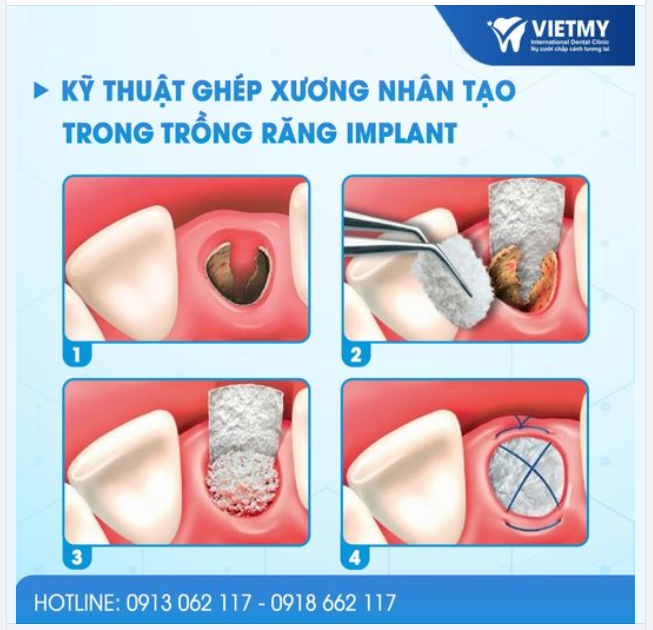

Trồng Răng Implant

Trồng Răng Implant -